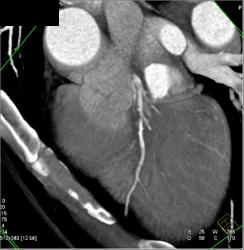

Diagnosis

Diseased LAD